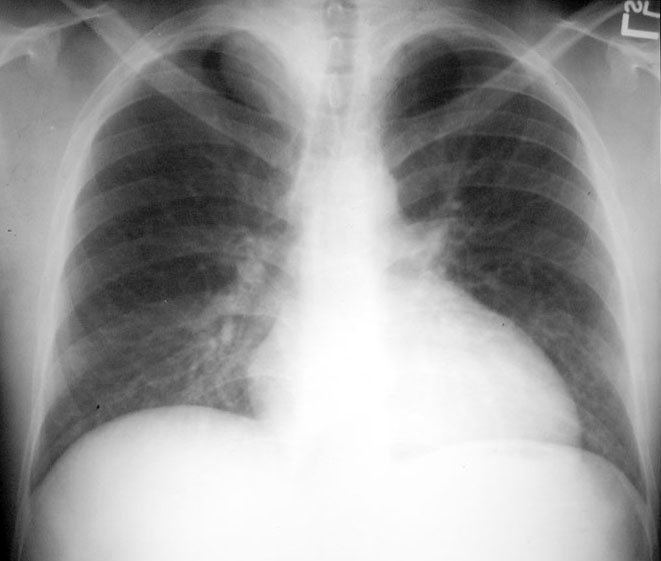

Cystic Hygroma

• Extrapleural sign

• Apical density on right

• Extending into neck